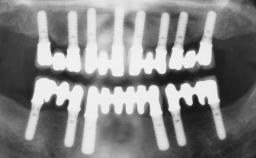

Conventional Loading of Eight Implants in the Maxilla and Final Restoration with a Full-Arch Gold-Ceramic FDP

# of Implants 8

Type of Implants One-Piece

Bone Augmentation Horizontal|Staged|Vertical

Augmentation Materials Autogenous block(s)

Prosthesis Type FDP